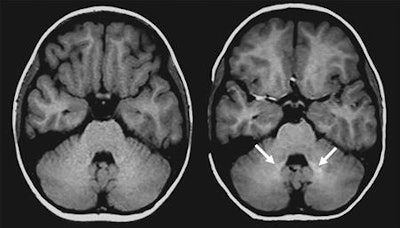

Young patients who received the gadolinium contrast agent showed greater signal intensity in the dentate nucleus on unenhanced T1-weighted MR images, compared with children who never received the contrast agent. The findings are of particular concern because pediatric brains are still developing, and these children may be exposed to additional gadolinium in future scans, depending on their illness.

Flood and colleagues discovered higher signal intensity in the dentate nucleus among patients who previously received multiple GBCA-enhanced exams (mean ratio, 1.046 ± 0.006), compared with subjects who had not received contrast (mean ratio, 1.007 ± 0.0058). This result is similar to what has been confirmed in adult patients.

However, there was no such signal intensity increase in the globus pallidus in the GBCA-exposed group (mean ratio, 1.014 ± 0.0091), compared with the GBCA-free subjects (mean ratio, 1.131 ± 0.0070).